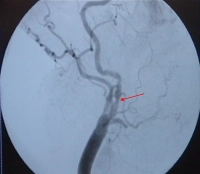

Perioperative management - Percutaneous transluminal angioplasty and stenting of the right internal carotid artery in recurrent stenosis– Vascular surgery

• High-grade recurrent stenosis (as in video example)

Digital subtraction angiography (DSA) of the arteries supplying the brain

• Only if the noninvasive procedures have proved inconclusive resulting in therapeutic consequences